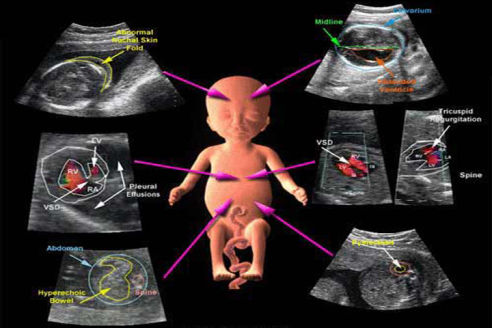

Early anomaly scan/Anomaly scan

Both Early Anomaly Scan and Anomaly Scan are ultrasound scans during pregnancy that help detect abnormalities in the developing fetus.